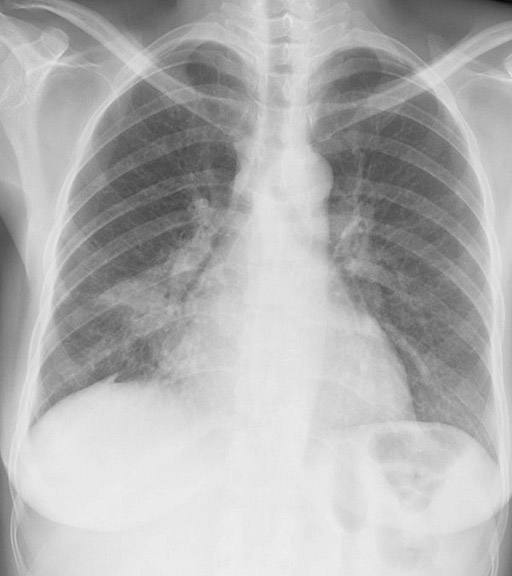

Gallery Lobar Collapse RML Collapse Case 1 PA

Case 1 PA